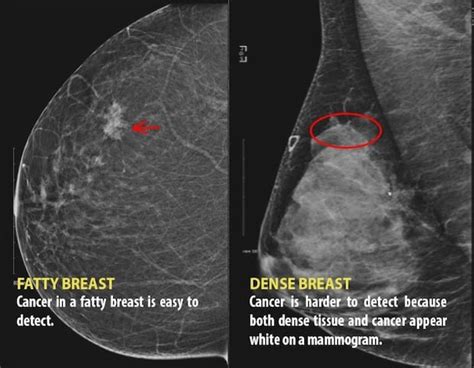

Breast density refers to the amount of fatty, fibrous, and glandular tissue present in the breast. Dense breasts have a higher proportion of fibrous and glandular tissue compared to fatty tissue. This increased density can make it more challenging to detect breast cancer through mammography, as the dense tissue can mask tumors. The American College of Radiology (ACR) categorizes breast density into four categories: almost entirely fatty, scattered areas of fibroglandular density, heterogeneously dense, and extremely dense.

Breast density is typically measured through mammography, which uses low-energy X-rays to produce images of the breast tissue. The resulting images are then categorized into one of the four breast density categories. Breast firmness, on the other hand, is often assessed through self-reporting or clinical examination. However, there is no standardized method for measuring breast firmness, making it challenging to draw conclusions about the relationship between breast density and firmness.

- Dense breasts have a higher proportion of fibrous and glandular tissue, which can make cancer detection more challenging.